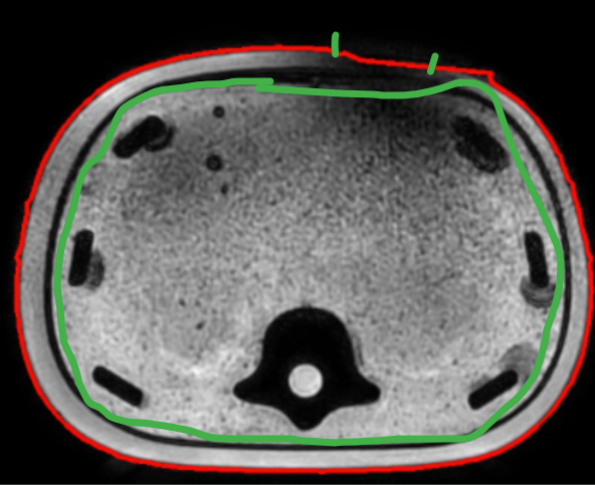

但实验中发现该方案有一个问题,它会抑制原本正常的“扩大”,”缩小“。如下图:

在数据集中的后边影像中,身体部分正常向外扩招,如上图蓝色区域,此时这部分会被检测为凹陷异常,那么就会用参考轮廓替代原本的蓝色轮廓。而且这种情况是累积的,因为身体向外扩展可能是连续的,所以如果当前层扩展失败,那么后面的更会失败,半径差会越来越大:

关键是”累积“的问题,这样抑制越来越大。